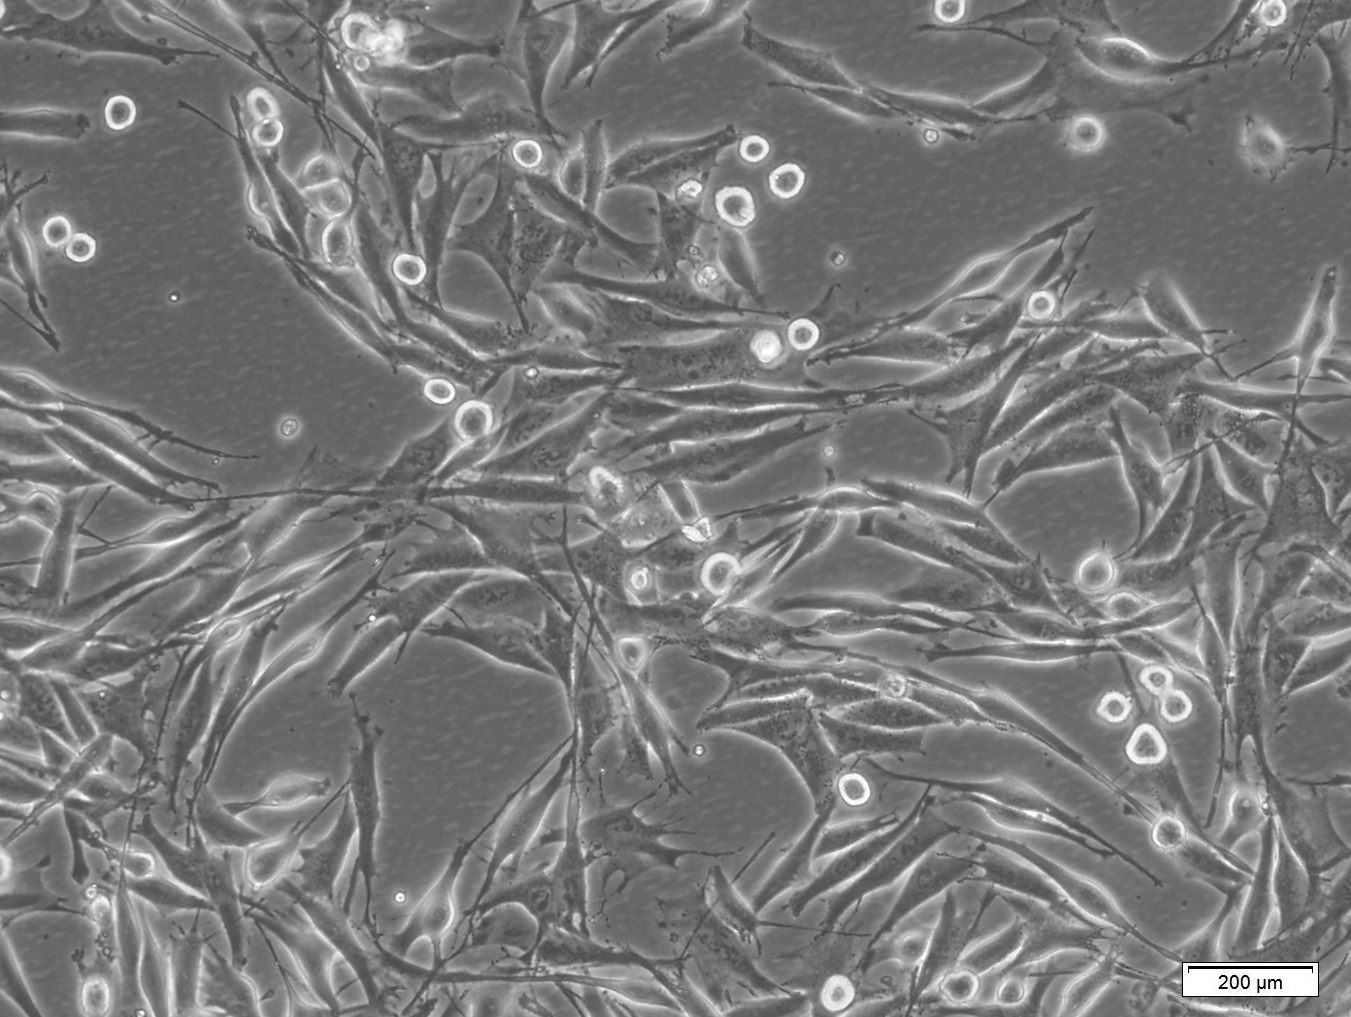

本细胞株的培养图片如下:

| Cell Line Name | A-375 (Human Amelanotic Melanoma Cells) |

贴壁

| Homo sapiens (Human) | Skin | Epithelial | Adherent |